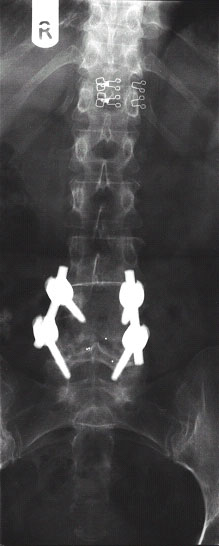

Abb.4-6

Seitliche Röntgenaufnahmen der selben Patientin nach der Operation (links) und nach einem Jahr (rechts). In jeden Wirbelkörper sind zwei Titanschrauben eingebracht (Bild mitte), verbunden sind die Schrauben mit jeweils zwei Titanstangen. Als Ersatz für die entfernte Bandscheibe dienen zwei Kunststoffwürfel (aus Carbon, erkennbar an punktförmigen Röntgenmarkierungen), welche mit dem Knochen des Patienten gefüllt sind. Auf dem rechten Bild ist die knöcherne Verbindung beider Wirbelkörper erkennbar.